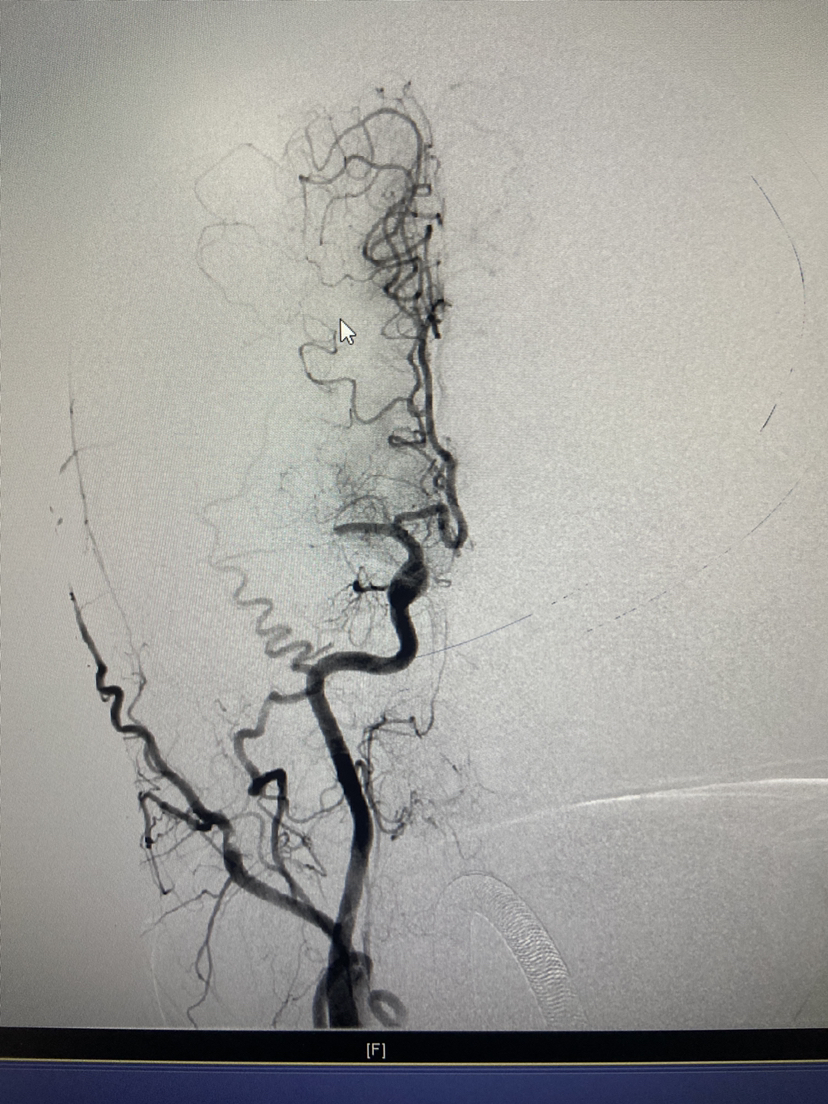

抽吸取栓一次再通